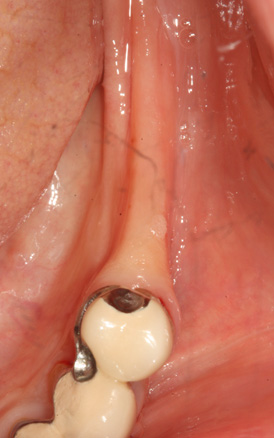

치조골 이식술 전후사진

B

A